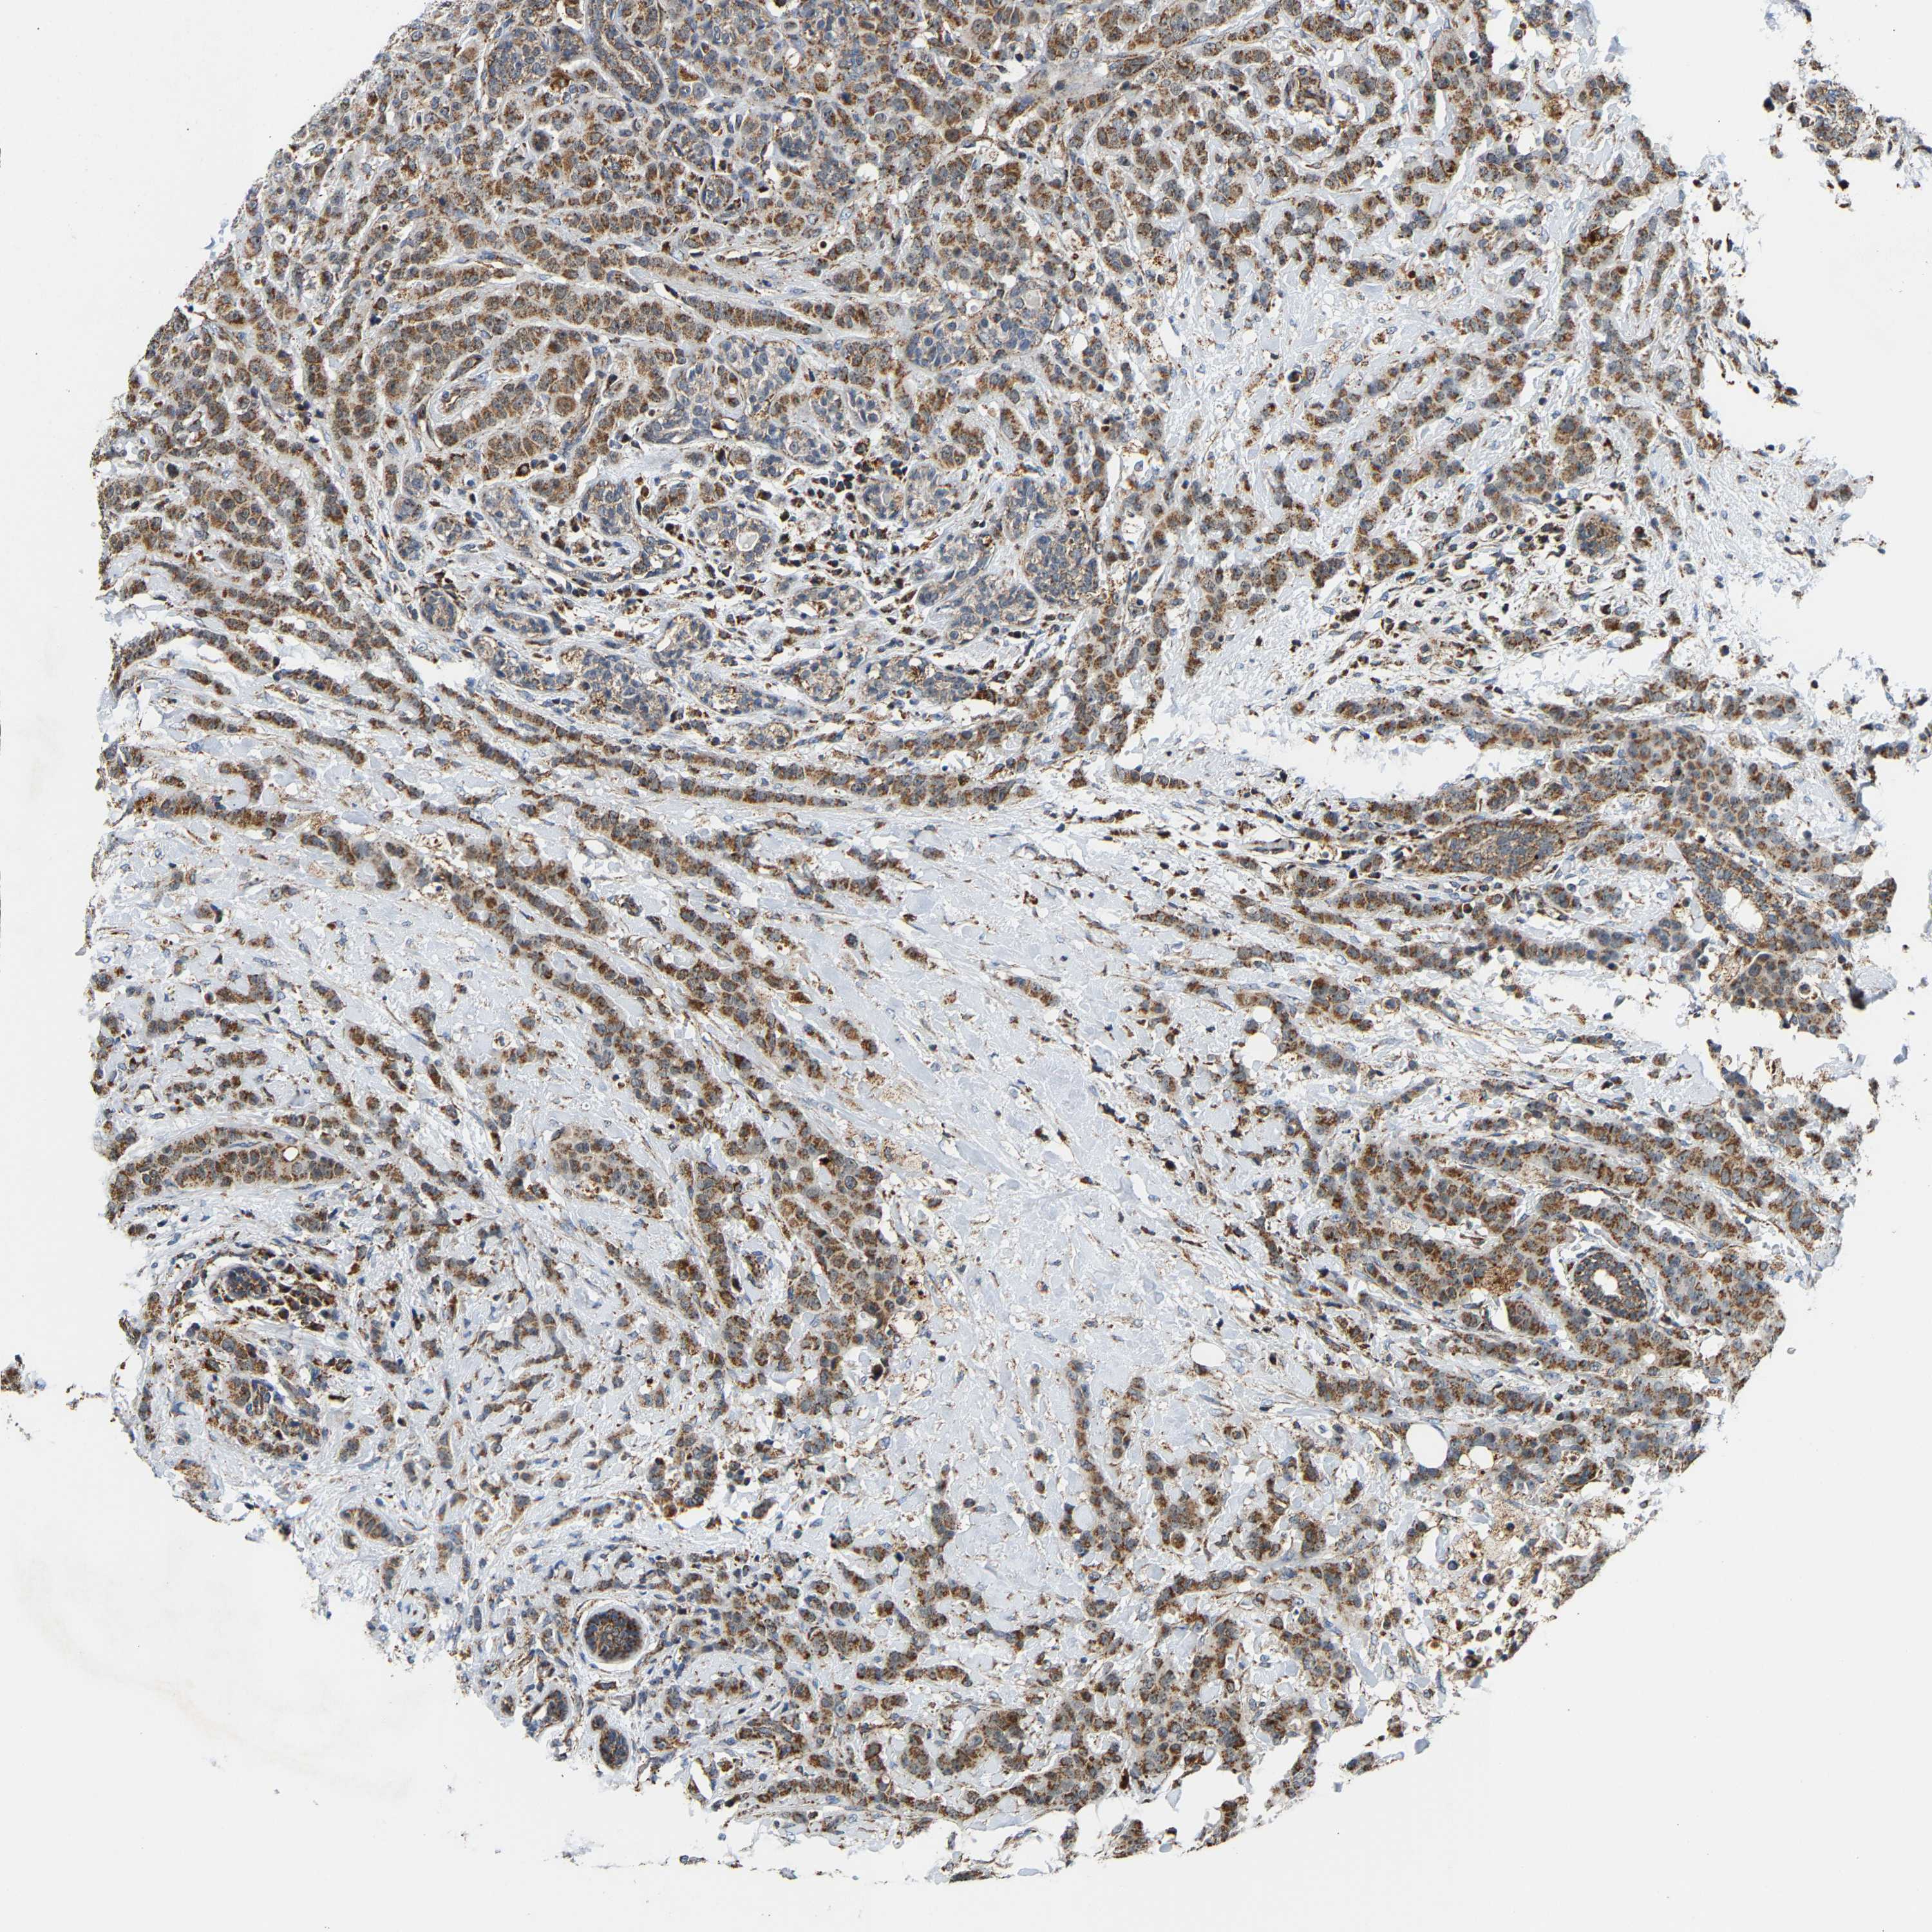

CANCER BREAST CANCER Show tissue menu

BRCA TCGA BRCA VALIDATION PROTEIN EXPRESSION